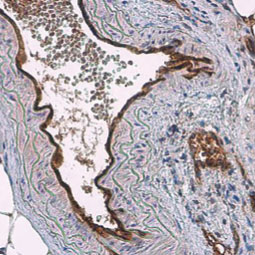

| 血管生成就是从预先存在的脉管系统中产生新血管,这是由促血管生成因子和抗血管生成因子输入严格控制的复杂过程,在正常成人中,这些诱导剂和抑制剂之间的平衡保持一种静止状态,尽管如此,它仍然能够响应因伤口、缺氧或炎症引起的微环境破坏而产生快速变化,在各种慢性病理状况和肿瘤中,这种平衡的扰动可导致不适当的血管生成或新血管形成,潜在的血管生成机制很复杂,但是调节这一过程的临床重要性意味着,这将仍然是引人注目的动态研究领域。 GeneTex提供广泛的研究抗体来支持血管生成的研究,请查看下面热门研究产品,或点击按钮以查看更多产品信息。 |